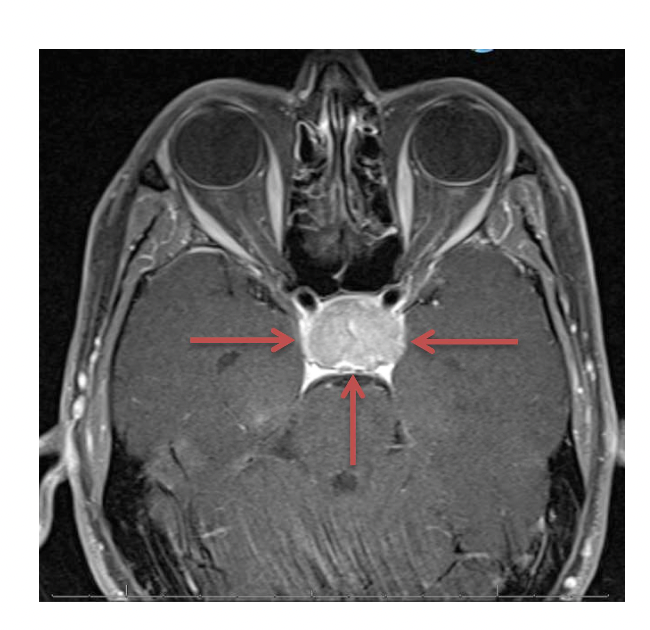

Du er øjenlæge:

En kollega beder dig kigge med på en MR scanning, som beskriver fund af et velafgrænset

adenom, men eksakt lokalisation er ikke anført i beskrivelsen (fremgår dog af billedet). Patienten

har bitemporal hemianopsi.

Hvilken del af den synsbanen er højst sandsynligt påvirket?